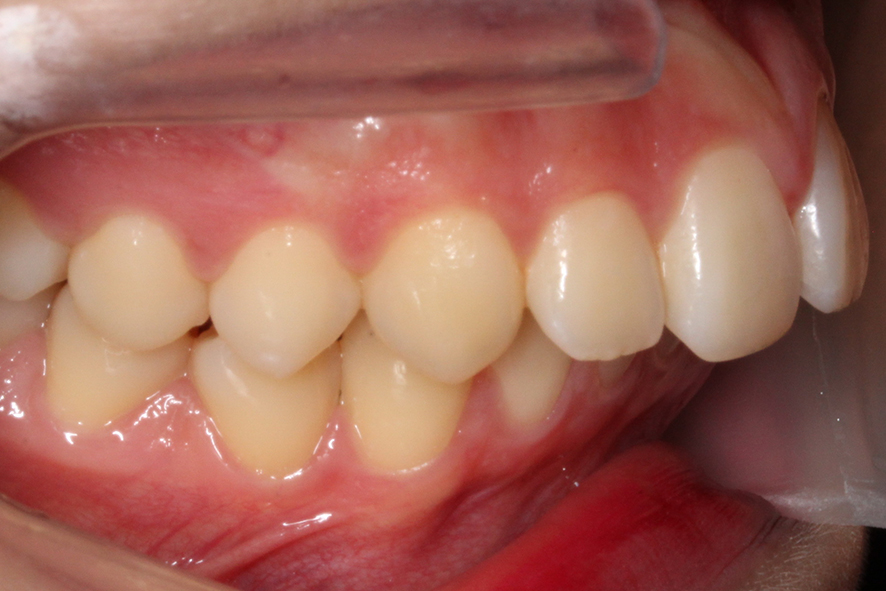

반대쪽 교합 평면 또한 상악 악궁의 길이가 길고

과도하게 발달하였기 때문에 어금니의

위치가 앞쪽으로 밀려나듯이 교합되는 모습입니다.